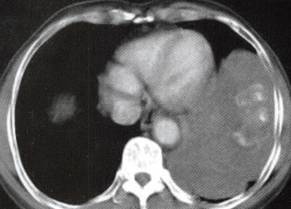

图1胸膜孤立性纤维瘤

A.B.CT平扫示左中下胸巨大肿块,宽基底与胸壁相连,内见斑片状钙化;

C~F.CT增强扫描肿块内缘肺门侧见一血管蒂样结构与纵隔相连,中度不均匀强化,内见匍行、紊乱的血管影,肿块中度均匀强化;

G.H.矢状位及冠状位重组见肿块与左膈面、左侧下胸壁宽基底相连,边缘胸膜掀起